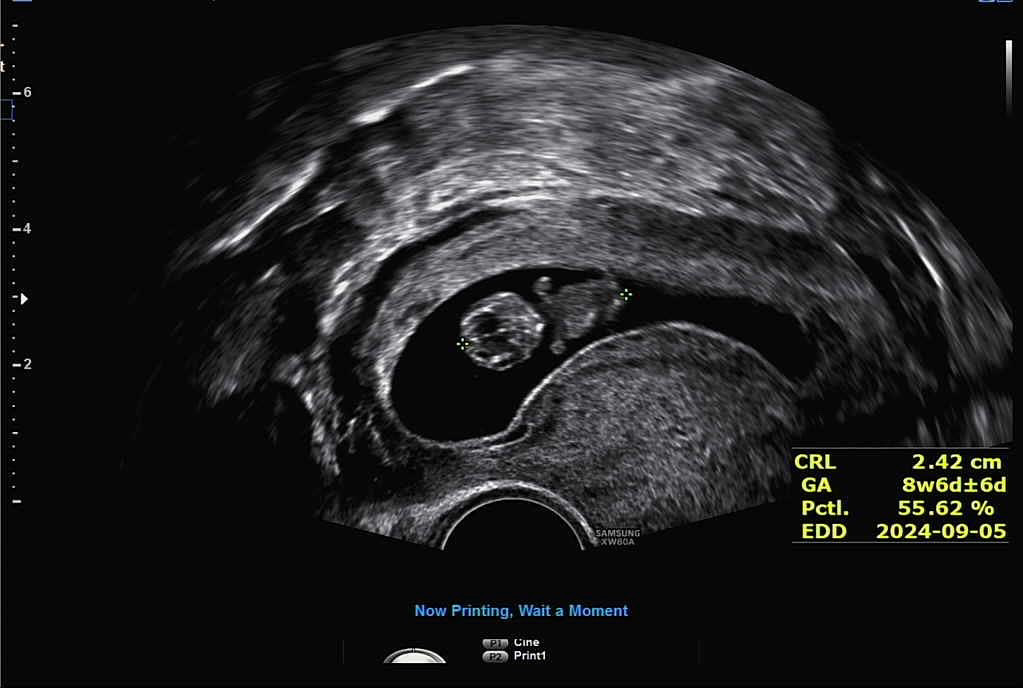

오늘 완벽한 젤리곰보고왔어요:)

9주0일로 팔다리 펄떡펄떡 하는것도 보고왔네용